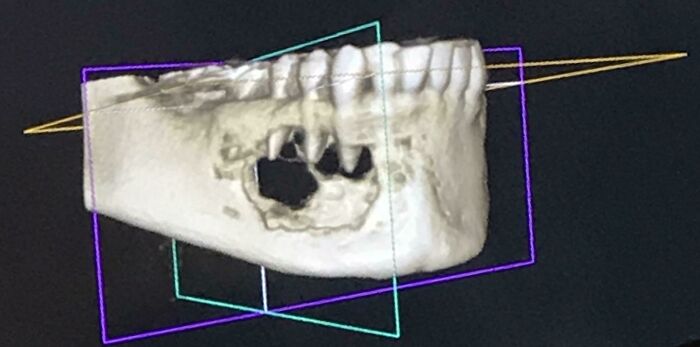

#6 Minulý mesiac som išiel na dentálnu hygienu a spomenul som pocit znecitlivenia v zube – bol som šokovaný, keď som zistil, že mi nádor požiera čeľustnú kosť